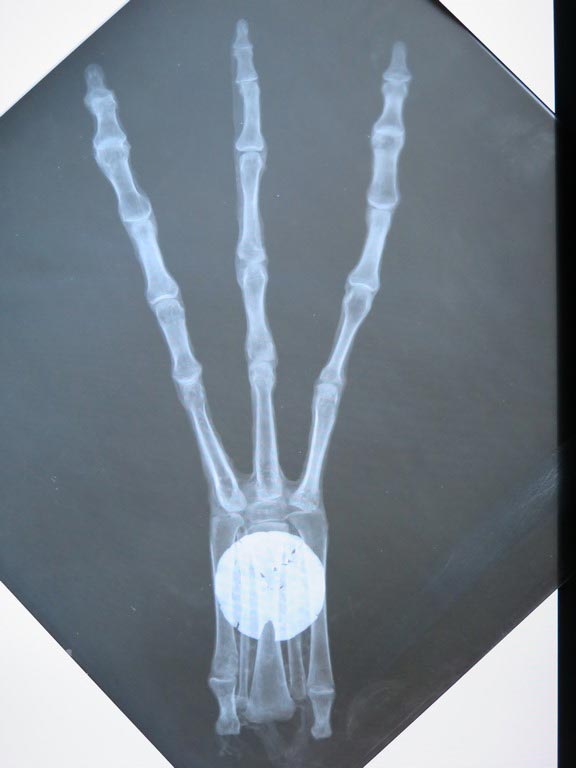

Pour écarter définitivement la thèse de la mutilation de corps humains (notamment pour créer les mains et pieds à trois doigts), le docteur David Ruiz Vela, chirurgien plasticien et médecin légiste, a apporté son expertise. Spécialiste de la microchirurgie et de la reconstruction des membres, il affirme que toute manipulation osseuse laisserait des traces indélébiles, visibles sur les tomographies haute définition.

Or, les articulations des momies montrent une harmonie structurelle parfaite. Les os longs contiennent de la moelle osseuse, prouvant que ces êtres ont été vivants. Le docteur Mendoza, radiologue chevronné, a également identifié des séquelles inflammatoires chroniques sur certaines articulations, comparables à celles laissées par la tuberculose, confirmant ainsi le vécu biologique de ces spécimens.